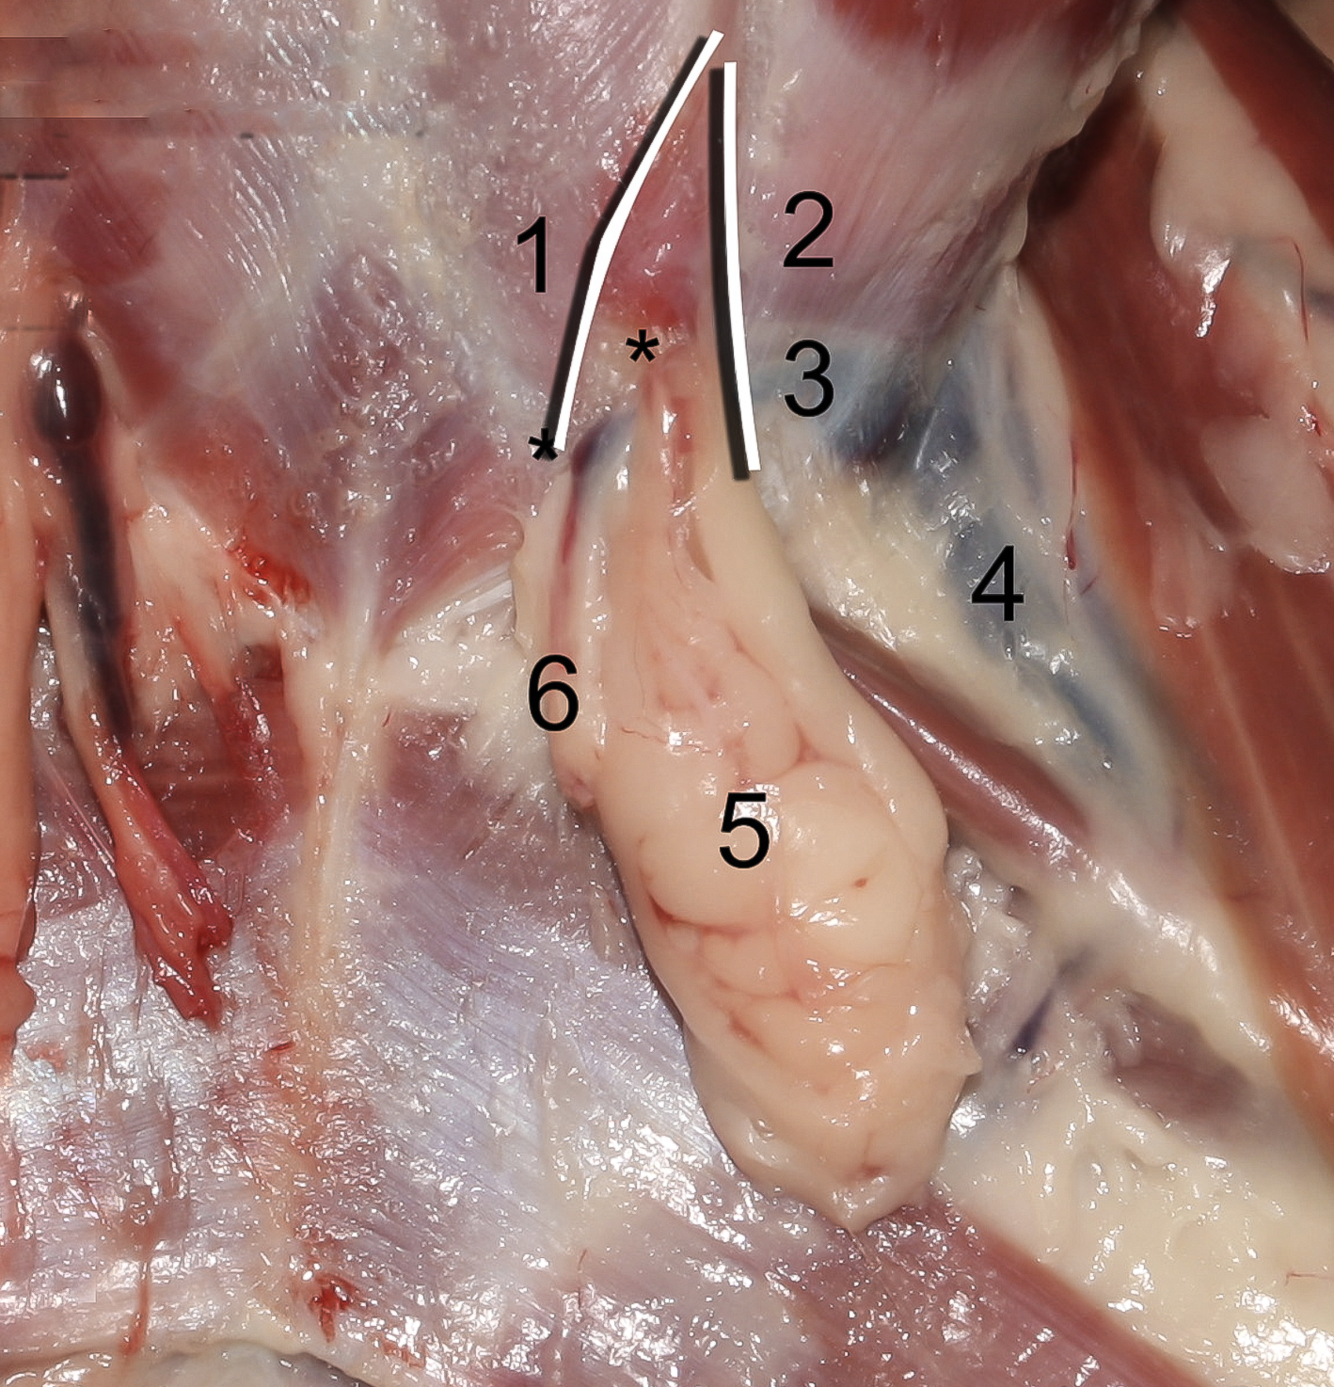

Q

1

A

Crus mediale

12

Q

2

A

Crus laterale

13

Q

3

A

A./v. pudenda externa

14

Q

5

A

Processus vaginalis

15

Q

6

A

M. obliquus internus abdominis

16

Q

Lig. Inguinalis

A